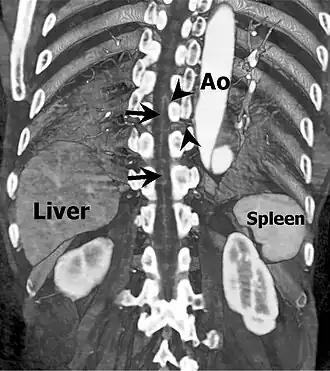

Coronal slab volume rendering image of CT aortography shows artery of Adamkiewicz entering spinal canal(arrowheads) and joining the anterior spinal artery (arrows) after a hairpin turn.

The artery has a characteristic "hairpin" turn on the cord surface as it first courses superiorly, then turns inferiorly. In 75% of people, it originates on the left side of the aorta between the T8 and L1 vertebral segments.[11] In addition to being able to be either right or left-sided, the vessel can arise from a lumbar artery instead of from the aorta.[5]